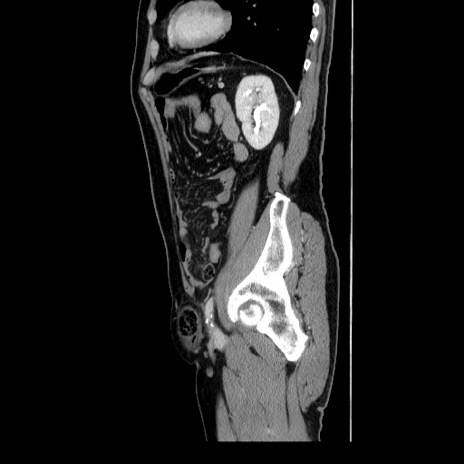

冠状断像

【症例】60歳代 男性

【主訴】右鼠径部膨隆

【現病歴】1年程前より右鼠径部膨隆あり。自己にて還納可能だったため放置していた。3時間前より右鼠径部の脱出を認め、還納困難となり受診。

【身体所見】右鼠径部に小児頭大の膨隆あり。弾性硬であり、用手還納は困難。左鼠径部にも膨隆を認める。脱出はなし。